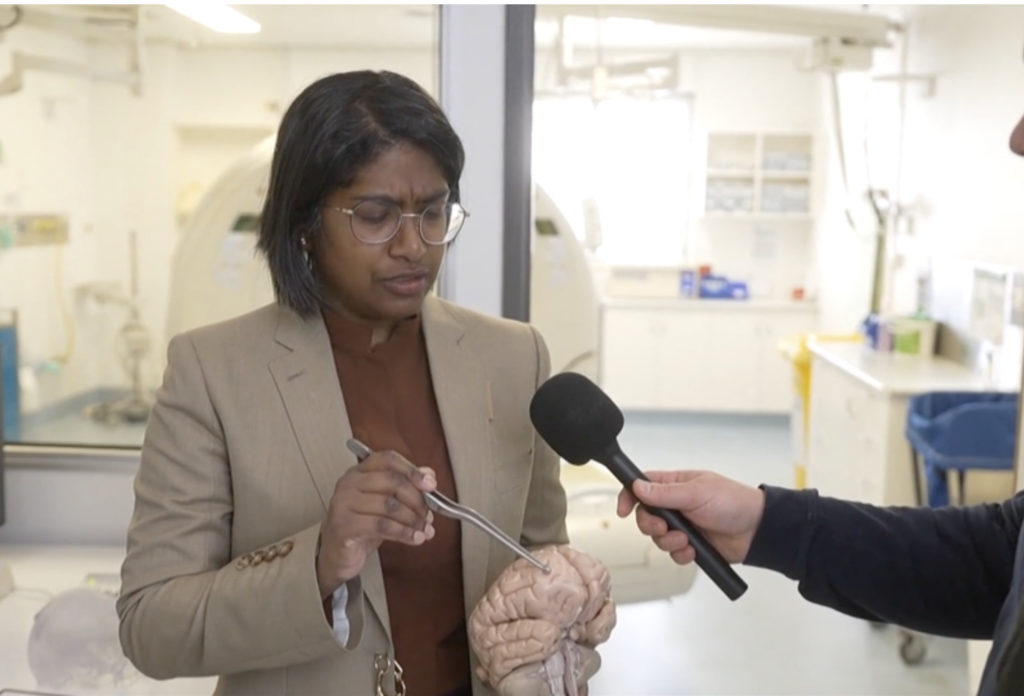

Indian Australian Neurosurgeon Dr Hari Priya Bandi shared her astonishment,

“I’ve only come across worms using my not-so-good gardening skills… I find them terrifying and this is not something I deal with at all.”

Dr. Bandi performed brain surgery on a 64-year-old woman and was taken aback when she pulled out an 8-centimetre (3-inch) long parasitic roundworm that was still wriggling between her forceps.

The parasite was identified as Ophidascaris Robertsi, a roundworm typically found in pythons, after a thorough examination and molecular tests.